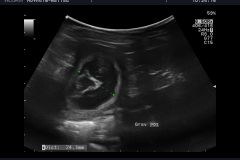

Das, was wir schon vermutet hattten, wurde uns heute, durch unseren Tierarzt bestätigt: Happy"ist trächtig . Wir werden um den 20.04.2024 Welpen in noir bekommen. Es wird für Happy ihr  letzter Wurf sein. Sie hat immer große Würfe gehabt und hat diese problemlos großgezogen. Wir hoffen und wünschen uns das es bei ihrem letzten Wurf auch so schnell, geht wie bei ihren beiden ersten Würfen. Namen mit L werden diesmal gesucht, drei Namen stehen schon fest La Luna , Le Soleil un L´Jiott.

Happy war es wohl zu heiß um im Hochsommer Welpen zu haben. Der Ultraschall hat ergeben, es gibt keine Welpen . Im Januar werden wir es wieder versuchen und bei Interesse können Sie sich gerne melden.